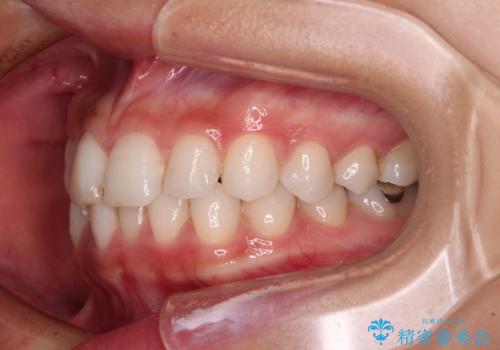

- 歯並びと虫歯をきれいにしたいとのことで来院された患者様です。

楽して短期間で歯列を整えたいとのことで、ワイヤー装置を用いて矯正治療を行い、矯正治療後に下顎の虫歯はセラミックインレー、上顎はPGAインレー(ゴールドインレー)、根管治療を行う歯についてはオールセラミッククラウンにて補綴治療を行うこととしました。

- 20代女性

矯正治療は8ヶ月ほどで終了し、速やかに虫歯治療に移行することができました。

保険治療で用いる樹脂(コンポジットレジン)で行った虫歯治療は、周辺が変色して汚くなっていましたが、下顎はセラミックインレーで審美的に、上顎はPGAインレーで歯に負担の少ない治療を行うことができました。